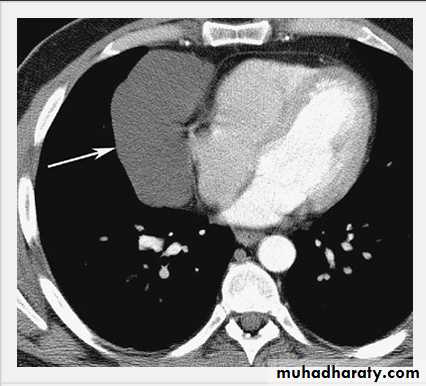

Pericardial Cyst.

Enhanced CT scan through heart shows a smooth, sharply marginated, low-attenuation mass (arrow) in the right cardiophrenic angle, consistent with a pericardial cyst.Neurofibroma.